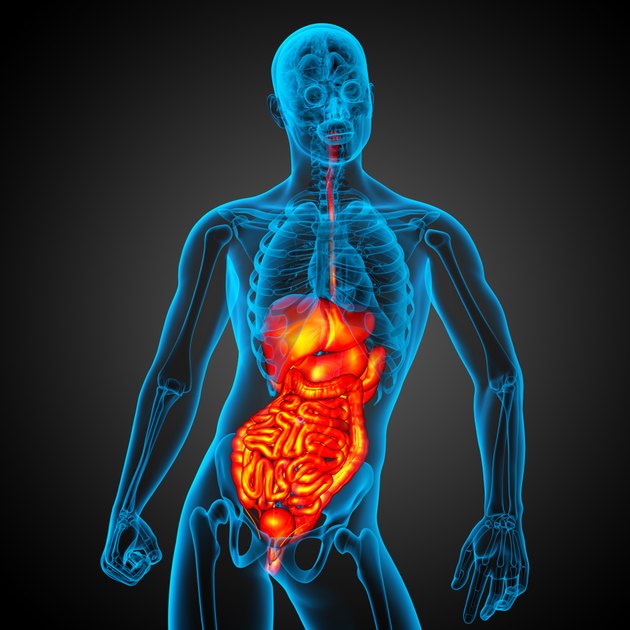

3D render medical illustration. (Source: SomkiatFakmee / iStock / Getty Images)

3D render medical illustration. (Source: SomkiatFakmee / iStock / Getty Images) Abdominal trauma can cause serious life-threatening injuries and may not be treatable because immediate symptoms may not be obvious. The membranous peritoneum surrounds some organs suspended from the abdominal wall, while the kidneys, pancreas, vena cava, aorta, and duodenum have additional protective effects. They are located in the retroperitoneal space and partially covered by the peritoneum. The lack of bone protection in the abdominal region makes the potential organs and surrounding structures vulnerable to blunt trauma. Although the damage may be small outside the body, there may be life-threatening internal injuries. During the initial examination, the examiner may ignore some of the subtle symptoms associated with abdominal damage. Therefore, it is important to conduct a series of inspections in hours and hours.